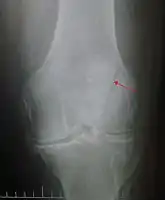

| Patella fracture | |

![]() | |

| A fracture of the patella seen on a lateral view | |